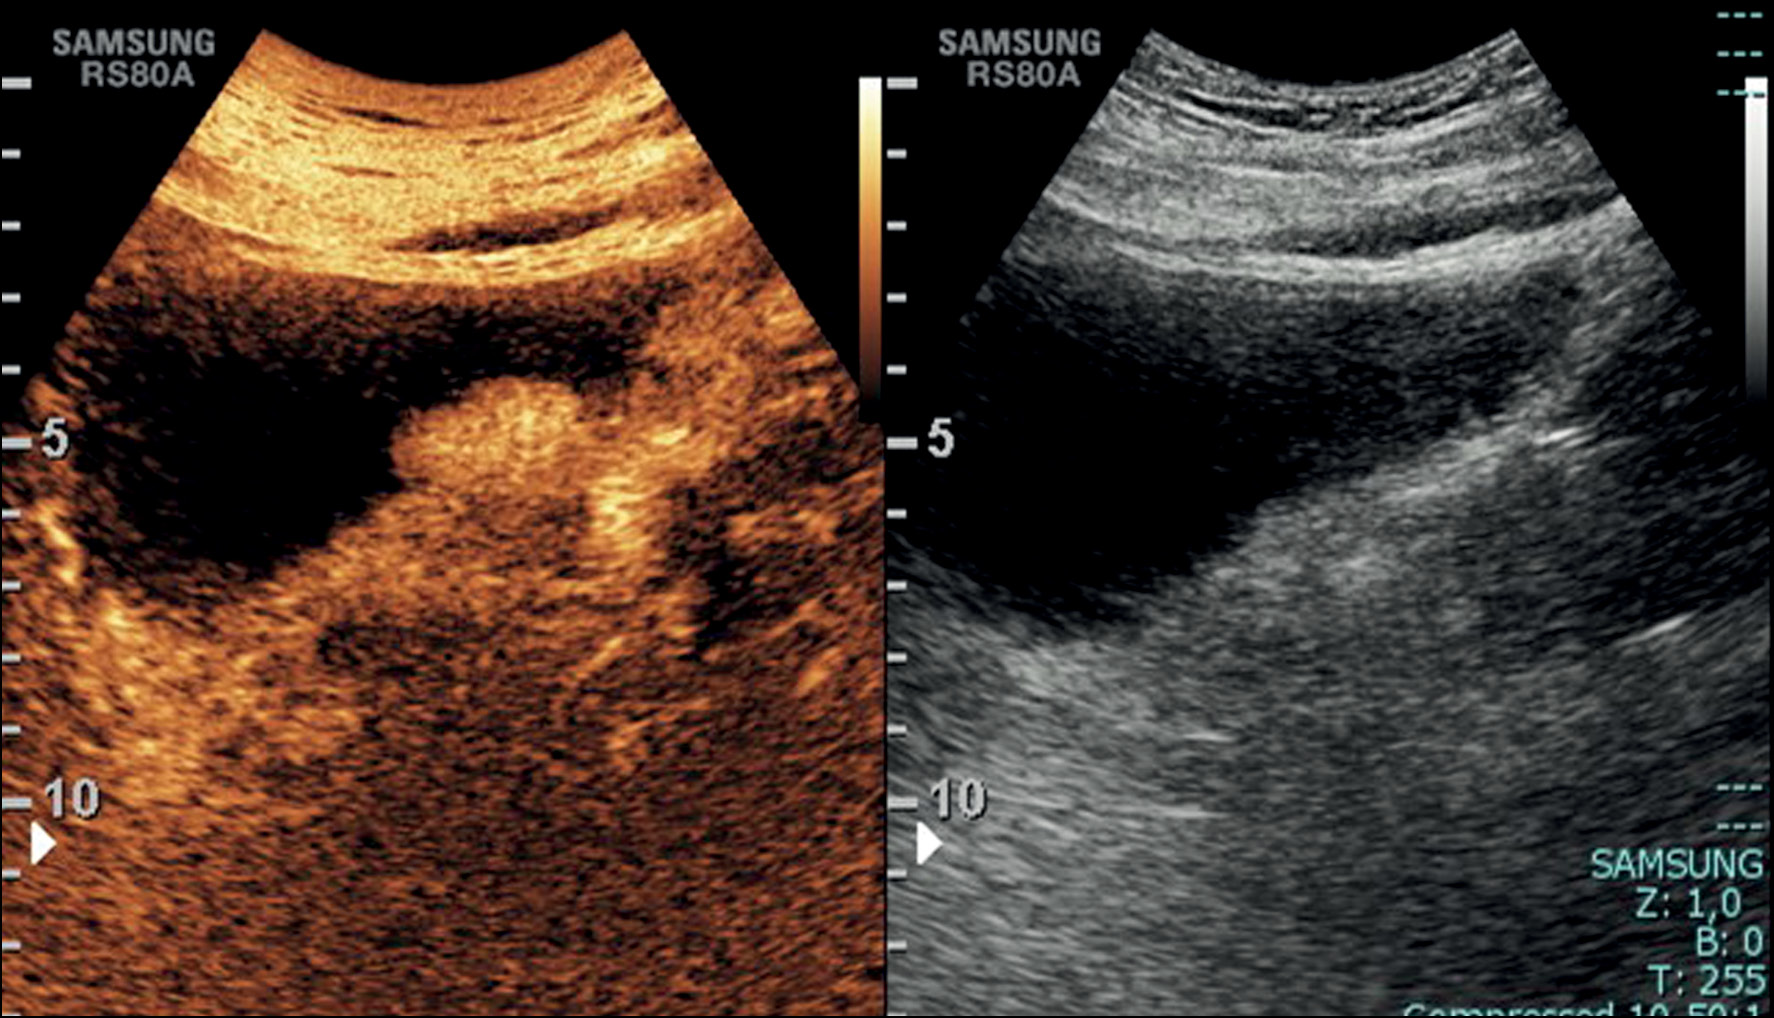

If a focal mass is detected in the US image, the presence of additional lesions must be further explored, considering that one-third of tumors are multifocal, and an additional evaluation with Doppler that helps in identifying the internal vascularity with a rich blood flow signal or a stellate morphology and differentiating a potential tumor from a blood clot. The latter can be excluded by asking the patient to change position from supine to lateral to assess for lesion mobility typical of a clot or performing bladder irrigation, followed by another US scan [11] (Fig.1).

Fig. 1. Transverse ultrasound image of the bladder showing diffuse irregular wall thickening with multiple masses and endoluminal development. Color Doppler on the largest echogenic lesion, localized on the left posterior bladder wall, showed vascularity within the mass.

Malignant bladder tumors exhibit distinct enhancement patterns compared with benign lesions, making CEUS a valuable tool for distinguishing between them and improving diagnostic accuracy. CEUS enables real-time observation of the blood flow in bladder tumors, aiding in the differentiation of benign from malignant tumors. However, compared with CT and MRI, its usefulness in bladder staging for infiltrating carcinomas is limited because it cannot assess perivesical fat infiltration and retroperitoneal lymph nodes (Fig. 2) [16].

Fig. 2. Sagittal contrast-enhanced ultrasound images showing an enhancing mass of the left bladder wall, not well definable in the B-mode as noticed on the left side of the image.